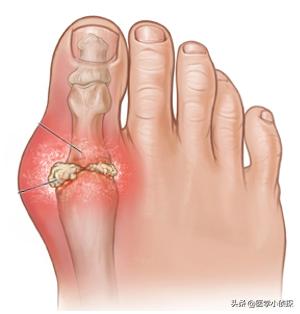

Il y a des nodules goutteux autour des articulations ou dans les perce-oreilles, et en cas de goutte de longue durée, les articulations sont atrophiées, déformées et souvent ulcérées, avec un écoulement crayeux des plaies.

On trouve des calculs de goutte sur le corps de presque toutes les personnes souffrant de goutte, et ils s'accumulent au fur et à mesure que la maladie évolue.fait des ravages dans les articulations de nos membres, entraînant des gonflements et des douleurs chroniques, des raideurs et des déformations, voire des fractures.

goutteIl s'agit d'une maladie causée par un taux élevé d'acide urique dans le sang qui entraîne le dépôt de cristaux d'acide urique dans les articulations, ce qui provoque des épisodes inflammatoires douloureux dans les articulations et autour d'elles. Les manifestations les plus typiques sontpierre de la goutte。

II. découverte des calculs de la goutte

Le site typique des calculs goutteux sous-cutanés est le pavillon de l'oreille, généralement autour des articulations récurrentes, de l'épervier, du tendon d'Achille et de la bourse rotulienne. L'aspect des organismes sous-cutanés surélevés de couleur jaune-blanc-rougeâtre et de taille variable, la surface de la peau est fine, et une matière blanche poudreuse ou pâteuse s'écoule après rupture, qui ne guérit pas sur une longue période de temps. Les calculs goutteux sous-cutanés coexistent souvent avec l'arthrite goutteuse chronique. Les dépôts importants de calculs goutteux dans les articulations peuvent entraîner une destruction des os de l'articulation, une fibrose des tissus périarticulaires et des changements dégénératifs secondaires.